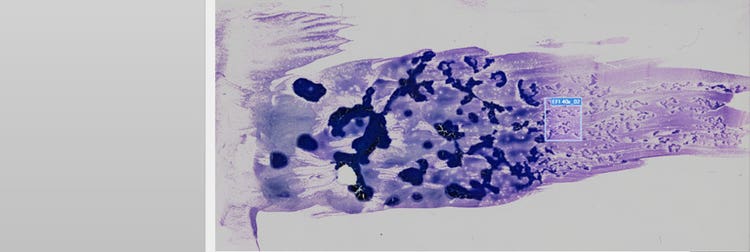

Whole slide imaging of a peripheral blood sample

Figure 1. Human peripheral blood sample of an acute promyelocytic leukemia scanned with the VS200 research slide scanner. Images courtesy of Jana Kirsten, Institute for Clinical Chemistry and Laboratory Medicine at the University Medical Center Regensburg.

In this application, the peripheral blood shows the neoplastic promyelocytes with bilobed nuclei or extreme granules (Figure 2, orange arrow). These neoplastic promyelocytes are also found in the bone marrow, as well as myeloid blast cells in which whole bundles of Auer rods (green arrow in A, B, and C) are located. These are important to look for if an APL is suspected.

Here’s a real example of how these magnifications are used. We scanned a human peripheral blood sample (Figure 1 below) of an acute promyelocytic leukemia (APL) using a 40X UPLXAPO oil objective with a 1.4 NA (Figure 2, A and C) and 60X UPLXAPO oil objective with a 1.42 NA (Figure 2, B and D).